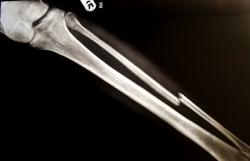

Les os sont durs et cassants. Lorsqu'un os se casse on appelle ça une fracture.